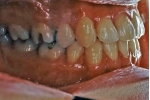

治療後3年経過時

|